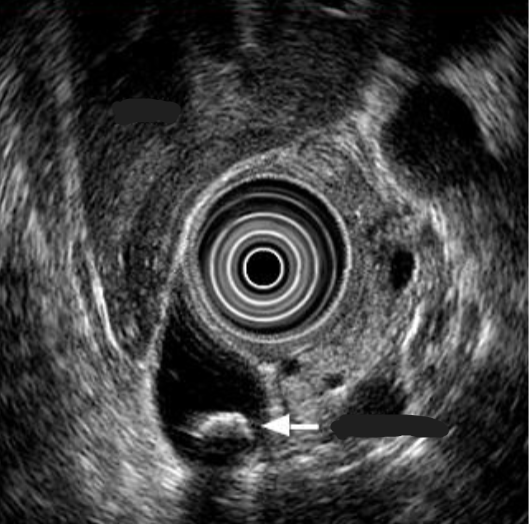

Endoscopic ultrasound

Transducer on tip of endoscope

More sensitive for sludge & small stones

Can exclude PUD

Endoscopic US

Endosonographic image of stone in common bile duct (with acoustic shadow)